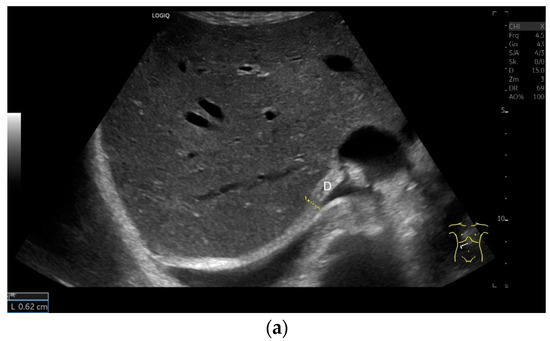

Subcostal transducer position: An abdominal sector or cardiac transducer (2–5 MHz) is used in the subcostal window. This position is used to assess diaphragmatic excursion. The transducer is placed between the linea medioclavicularis and linea axillaris anterior. The diaphragmatic excursion can then be visualized and measured in M-mode (Figure 5). The gallbladder and inferior vena cava are important landmarks. It is important to guide the ultrasound probe as perpendicularly as possible. The M-mode axis should meet the diaphragm at an angle of 90%. In this position, diaphragm thickness in inspiration and expiration can also be measured using M-mode, and diaphragm shortening can be calculated. However, in normal adults, the diaphragm can usually only be visualized in this position using abdominal sector transducers and is less accurately delineated than with a linear transducer from the lateral side in the anterior axillary line.

Subxiphoid: The diaphragm can be positioned directly subxiphoidally with a slightly sagittal transducer position on both sides next to the attachment to the sternum. The diaphragm limb can be demarcated to the right in the epigastrium in cross section between the aorta and the inferior vena cava. However, this is primarily of differential diagnostic importance, e.g., in relation to lymphomas, not for the actual assessment of the diaphragm (Figure 6).